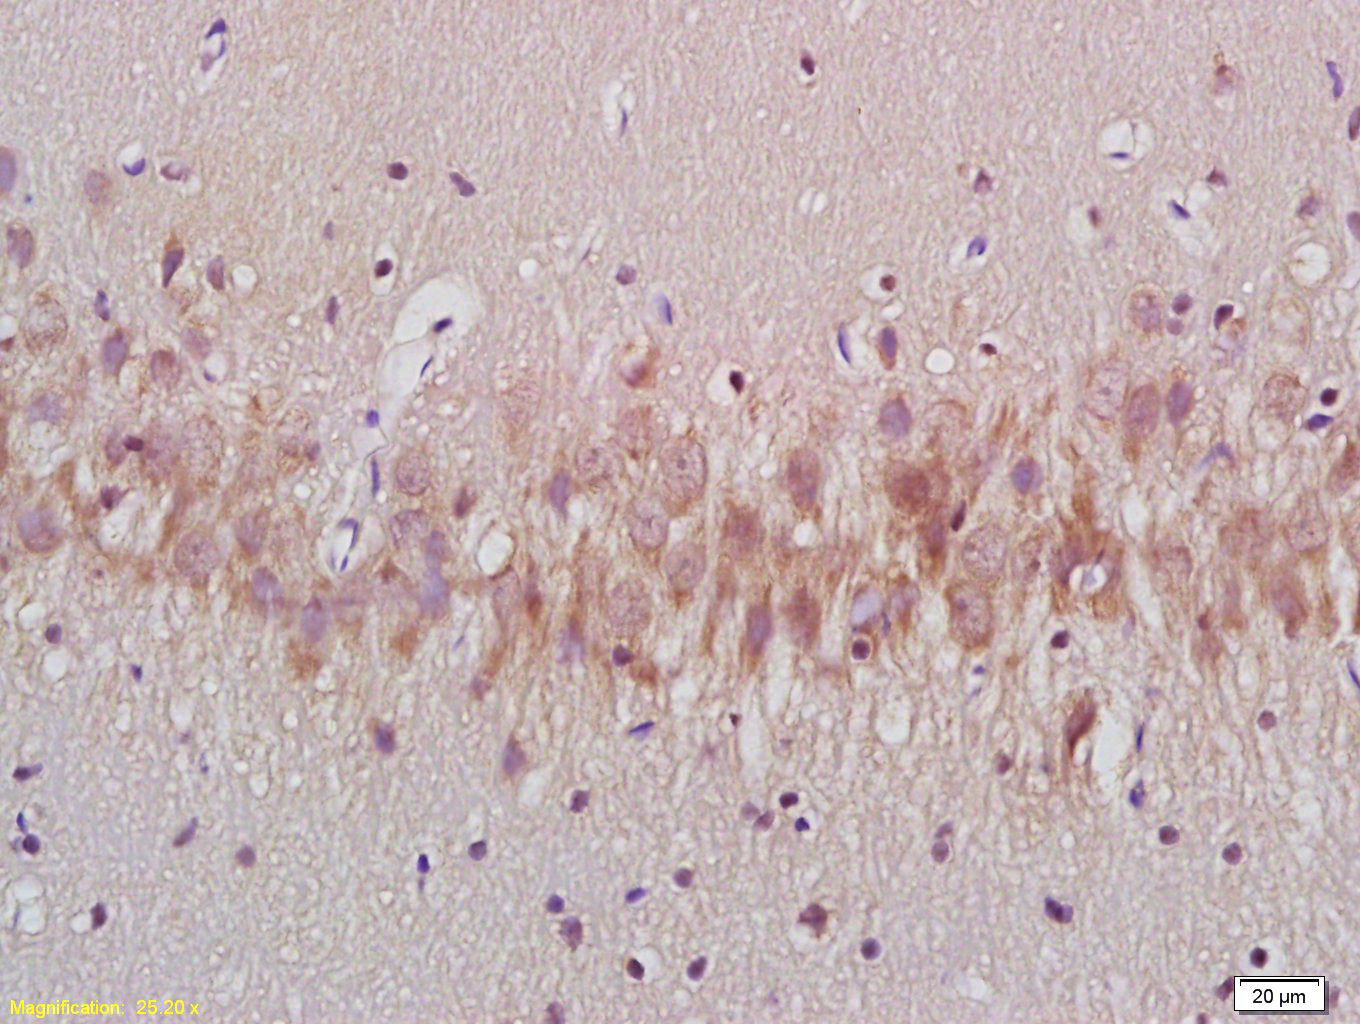

Tissue/cell: rat brain tissue; 4% Paraformaldehyde-fixed and paraffin-embedded; Antigen retrieval: citrate buffer ( 0.01M, pH 6.0 ), Boiling bathing for 15min; Block endogenous peroxidase by 3% Hydrogen peroxide for 30min; Blocking buffer (normal goat serum,C-0005) at 37℃ for 20 min; Incubation: Anti-phospho-Tau protein(Ser404) Polyclonal Antibody, Unconjugated(bs-2392R) 1:200, overnight at 4°C, followed by conjugation to the secondary antibody(SP-0023) and DAB(C-0010) staining